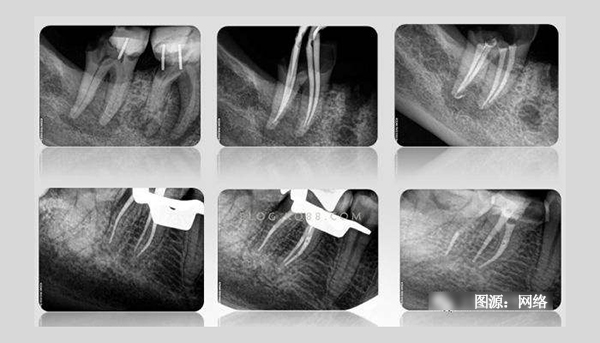

有根管治疗史的患者都知道,在根管治疗过程中需要反复拍摄多次X光片。一般说来,完成一颗牙的根管治疗至少需要3张X光片:术前X光片、术中X光片、术后X光片。

术前X线片反映患牙及牙周组织的客观情况—根管长度、根尖周牙槽骨密度等,目的主要是帮助牙医了解患牙的病变范围、牙根情况、根管数目以及根尖周病变情况,根管是否存在钙化,帮助医生判断患牙的预后以及根管治疗的难度,是牙科治疗的依据。

术中需要对根管预备情况进行检查,主要是辅助测量根管长度,看根管预备是否到位,牙齿里面的神经是否清理干净。对于难度较大者需要一边进行根管预备一边插针拍X线片,以监测根管预备的方向和程度以求良好的治疗效果。

术后X线片是为了观察根管治疗是否彻底,根管内充填物是否合适,判断根管治疗充填的质量是否到位。术后拍摄X线片,有助于医生对治疗效果的判断,如果治疗结果不满意可及时更正,以免出现不必要的复诊。根管治疗术后拍X线片片已成为检验根管治疗质量的手段之一,是根管治疗规范化操作的一部分。